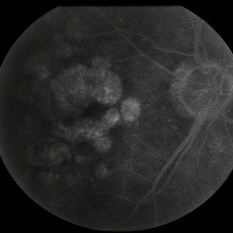

---thumb.jpg/image-square;max$300,300.ImageHandler) Age Related Macular Degeneration

Age Related Macular Degeneration

May 3 2013 by Suber S. Huang, MD, MBA, FASRS

Age related macular degeneration.

Condition/keywords: advanced geographic atrophy, atrophic scar, atrophic spot, geographic atrophy, macula lesion, pigment epithelial atrophy, red-free, window defect